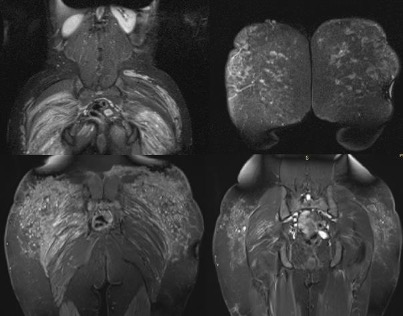

La resonancia magnética (RMN) es fundamental en el proceso de extracción de biopolímeros, porque permite identificar con exactitud la localización, volumen y nivel de infiltración de los biopolímeros en los tejidos.

A diferencia de otros estudios de imagen como la ecografía o la tomografía computarizada, la resonancia magnética es el único método que proporciona una visualización detallada de los biopolímeros y su impacto en los tejidos circundantes.

• Permite localizar con precisión los biopolímeros y su distribución en el tejido.

• Determina el grado de migración del material hacia áreas como la parte baja de la espalda, muslos o región lumbar.

• Ayuda a identificar procesos inflamatorios crónicos, fibrosis o necrosis en la zona afectada.

• Generalmente se enfoca en la región glútea y zonas circundantes donde pueda haber migración del material.

La Resonancia Magnética es una herramienta fundamental en la extracción de biopolímeros, ya que proporciona información detallada sobre la ubicación y el estado de estas sustancias modelantes en el cuerpo.

Su uso permite una planificación quirúrgica precisa, reduce el riesgo de complicaciones y mejora los resultados postoperatorios. En este tipo de cirugías, optar por una resonancia de 3 Teslas es clave para garantizar un diagnóstico exacto y una intervención segura y efectiva.